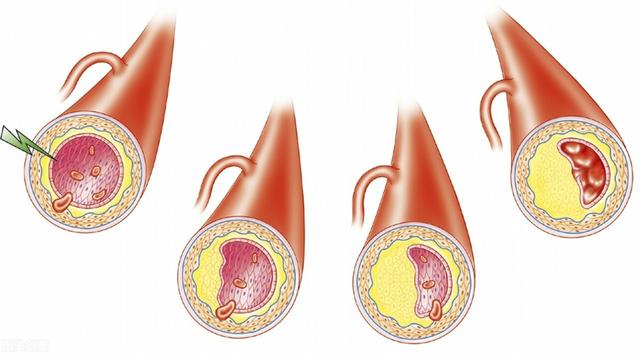

最初の状況は急性心筋梗塞である。冠動脈の動脈硬化が進行し続けると、冠動脈に脂質が沈着して形成されたプラークが徐々に変化し、一部の不安定なプラークが特定の要因の影響を受けてプラークの破裂が起こると、血液中の凝固物質が凝集して血栓が形成され、冠動脈の血管が閉塞し、心臓の血液供給に深刻な影響を及ぼし、重篤で緩和困難な狭心症、胸部圧迫感、心筋梗塞に関連する症状を引き起こす可能性があります。心筋梗塞に関連する症状として、死が近いという感覚などがある。

(2) 動脈硬化:冠動脈性心疾患とは、血液中の脂質成分が内皮細胞の下に侵入し、炎症反応が起こり、動脈硬化性プラークが形成されることによって引き起こされる病気のことである。

(1) 急性冠症候群:病院の胸痛センター(救急外来)で毎日診察される冠動脈性心疾患で最も多いのが急性冠症候群である。実際には冠動脈のアテローム性動脈硬化プラークが何らかのきっかけで不安定になり、プラークが破裂して血栓症を誘発し、血流が突然途絶えるか途絶えそうになり、心筋に突然血液が供給されなくなり、心筋梗塞が起こります。この時、狭心症が20分以上続き、ニトログリセリンを3回連用しても緩和されないことが多いので、注意が必要で、心筋梗塞の可能性があり、一刻も早く120番救急ダイヤルに電話する必要があり、2時間以内に病院に到着し、血管を開くのが最善で、最も効果的な方法の一つはステント留置術である。もちろん、ステント治療が行えない病院では、血栓溶解療法が禁忌でなければ、時間を稼ぎ、その後の診断と治療の機会を作るために、血栓溶解療法も選択肢となる。

- プラーク表面の潰瘍やプラーク破裂などのプラークの不安定性は血小板凝集を引き起こし、血管の狭窄を増大させる。

- 元のプラークの狭窄が70%であったとすると、プラークが安定していれば、患者に症状はない。しかし、プラークが破裂して血栓が形成され、血管が100%狭窄すると、患者は突然持続性狭心症を発症し、急性ST上昇型心筋梗塞となる。

冠動脈性心疾患とは、冠動脈アテローム性動脈硬化性心疾患の略称であり、主に心臓に血液を供給する動脈である冠動脈のアテローム性動脈硬化によって引き起こされる。動脈にアテローム性動脈硬化症が起こると、動脈の内表面にプラークが形成され、プラークが蓄積するほど動脈の直径が狭くなる。狭窄の程度が50%未満であれば、心筋への血液供給には影響しないので、一般的に症状はありませんが、50%以上になると、心筋への血液供給に影響を及ぼし、心筋の酸素消費量が増加しても、心筋が十分な酸素を得ることができず、心筋虚血、低酸素状態になると、胸部圧迫感、胸痛の症状が誘発され、これを狭心症と呼びますが、狭心症の症状は活動を停止すると徐々に緩和されます。狭窄の程度がさらに悪化したり、局所的なプラークの破裂、冠動脈の血栓閉塞によって心筋虚血が生じたりすると、狭心症の程度はさらに悪化し、緩和されない状態が続き、閉塞が解除されなければ心筋虚血壊死を引き起こし、ついには患者の突然死に至ることもあり、これが心筋梗塞と呼ばれるものです!